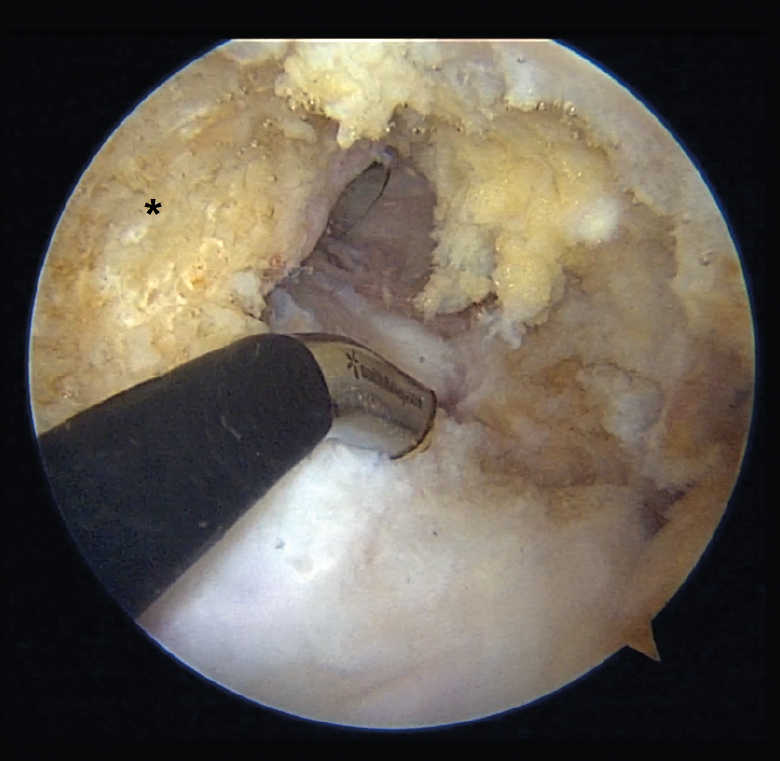

Arthroscopic portals

Depending on the preferences and experience of the surgeon, reconstruction of the PCL can be made through different portals. The standard anteromedial and anterolateral portals are routinely used for joint revision surgery and the treatment of associated chondral, ligamentous or meniscal lesions. Some authors use posteromedial and posterolateral portals to adopt a trans-septal approach (Kim's technique) and thus work exclusively from the back of the knee. Other surgeons prefer a portal through the patellar tendon (Gillquist portal) in combination with a posteromedial portal, alternating them as viewing and working portal. Utilization of the transpatellar portal is simpler in the case of combined rupture of the ACL and PCL, since the intercondylar space is completely vacant (Figure 8)(23).

Figure 8. "Vacant" intercondylar space in combined rupture of the anterior cruciate ligament (ACL) and the posterior cruciate ligament (PCL) in a left knee. The surgeon is using the transpatellar (Gillquist) portal for viewing and the anteromedial portal for working with radiofrequency. The working cannula placed in a posteromedial portal can also be seen. The black asterisk indicates the lateral wall of the medial femoral condyle, as the femoral insertion site of the PCL.